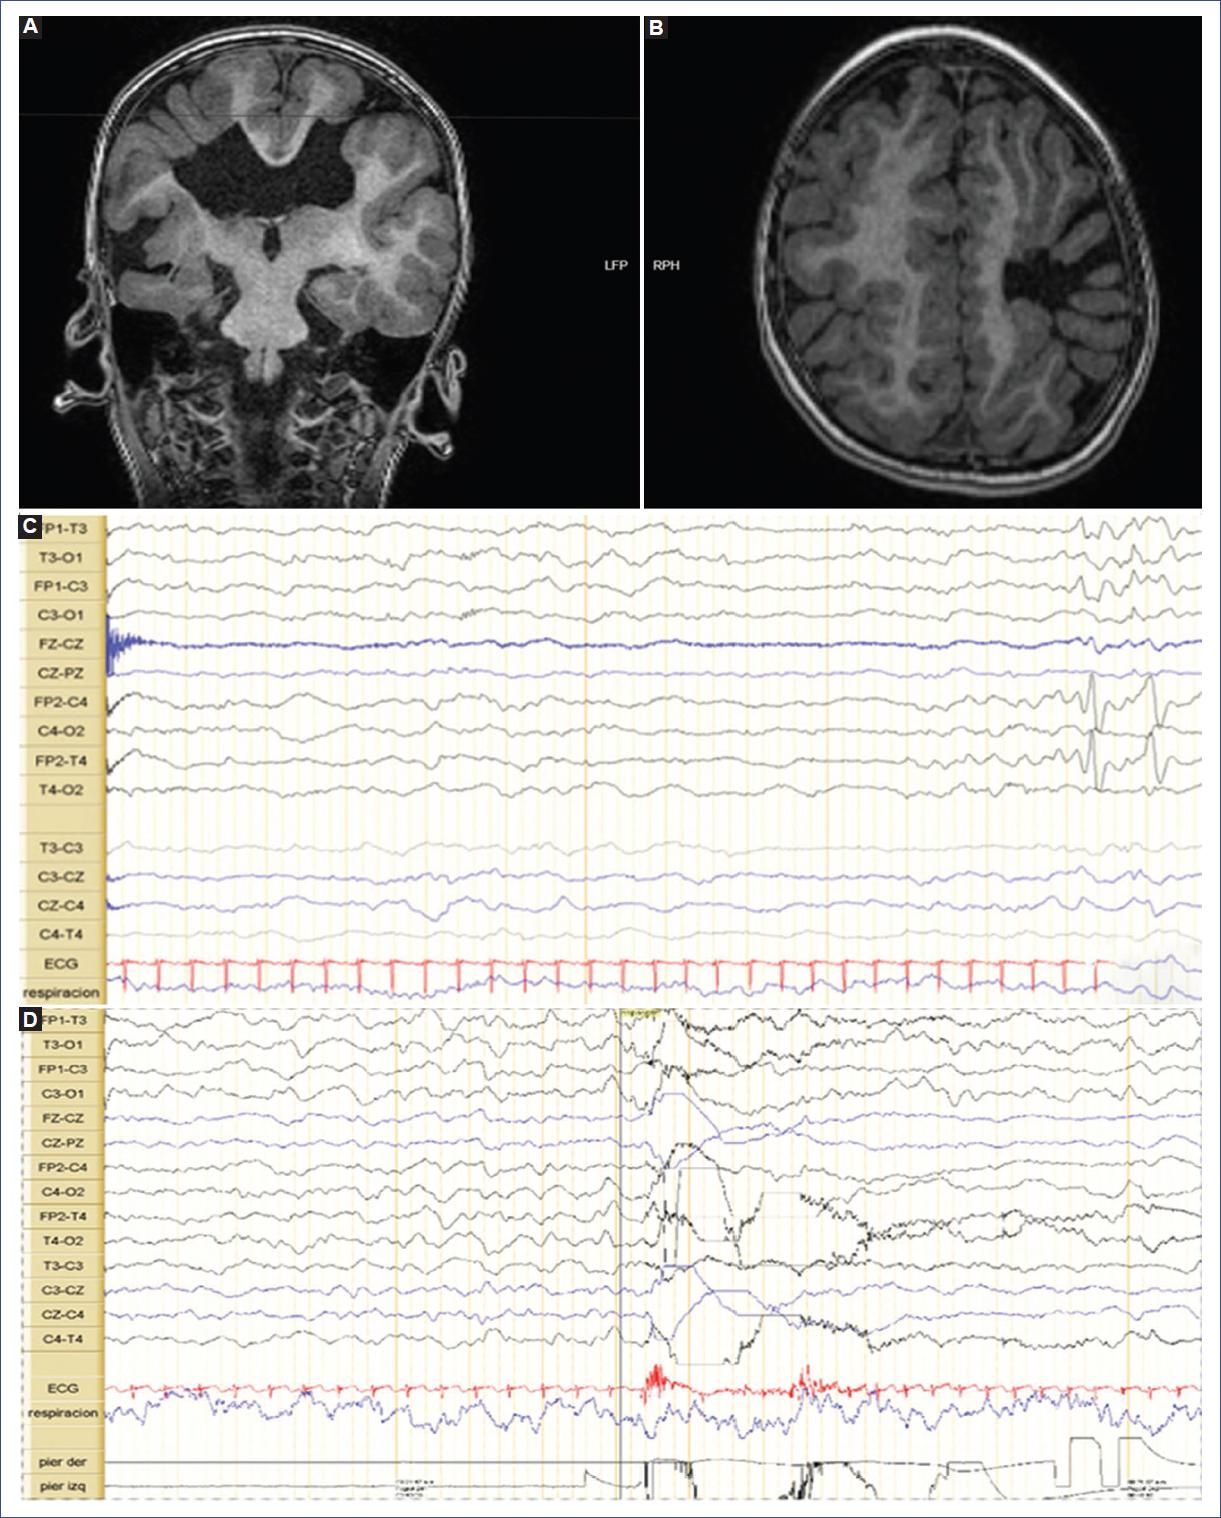

Recién nacida de sexo femenino, producto de madre de 19 años, G1C1V1, con diagnóstico prenatal en la semana 25 de malformación cerebral tipo esquizencefalia del lado izquierdo. Estudio de TORCH negativo. Niega consumo de medicación por patologías y de drogas psicoactivas. Parto por vía cesárea en la semana 36 debido a presentación podálica y estado fetal no satisfactorio. Al nacimiento, peso de 1940 g, talla de 48 cm y perímetro cefálico de 30.5 cm (Z: −1.19 SD Fenton). Presentó cianosis temprana, hipotonía y esfuerzo respiratorio pobre, por lo cual se inició ventilación a presión positiva, con mejoría progresiva. Apgar de 2, 5 y 10 a 1, 5 y 10 minutos de vida, respectivamente. En la exploración clínica se evidenció retraso del crecimiento intrauterino simétrico, soplo cardiaco II/VI, pie equino varo bilateral y leve hipotonía. Al día 2 de vida se le realizó una TC de cráneo simple que reportó doble esquizencefalia frontal izquierda de labio abierto y esquizencefalia de labio abierto en la transición parietooccipital-temporal derecha, displasia del septo interventricular y adelgazamiento del cuerpo calloso. Ambulatoriamente se realizó una RM cerebral que corroboró los hallazgos de esquizencefalia frontal bilateral, ambas de labio abierto, rodeadas de sustancia gris heterotópica de predominio izquierdo y asociadas a polimicrogiria frontoparietal bilateral de predominio izquierdo, ausencia de cavidad del septo pelúcido y ligera irregularidad del nervio óptico izquierdo (Fig. 2 A y B). El tallo cerebral, el cerebelo y los núcleos grises de la base no mostraban otras alteraciones. Se realizó un primer videoelectroencefalograma que reportó buen patrón de sueño y vigilia para la edad, con ocasional actividad epileptiforme sobre la región centrotemporal derecha, sin evoluciones ictales ni crisis clínicas (Fig. 2C). La paciente evolucionó durante sus primeros días de vida con estabilidad cardiopulmonar y progresión de tolerancia al aporte enteral sin complicaciones. No hubo deterioro neurológico, con adecuada succión y sin crisis clínicas. Se inician terapias de rehabilitación integral y es dada de alta con indicación de seguimiento por neuropediatría. Durante los controles se evidenciaron espasmos infantiles y videoelectroencefalograma 1 mes después con patrón de hipsarritmia (Fig. 2D), por lo que requiere tratamiento anticonvulsivante con vigabatrina a dosis inicial de 50 mg/kg/día, logrando un aceptable control de las crisis.

Figura 2 Caso 2. A y B: resonancia cerebral simple, cortes coronal y axial. Se observan esquizencefalia de labio abierto en las regiones frontal izquierda y en la transición parietotemporal derecha, con polimicrogiria frontoparietal bilateral de predominio izquierdo y ausencia del septo pelúcido. C y D: videoelectroencefalograma que muestra actividad interictal ocasional en forma de complejo punta onda irregular de mediana amplitud en la región centrotemporal derecha (C), y registro de espasmos epilépticos (D) sin patrón de hipsarritmia.